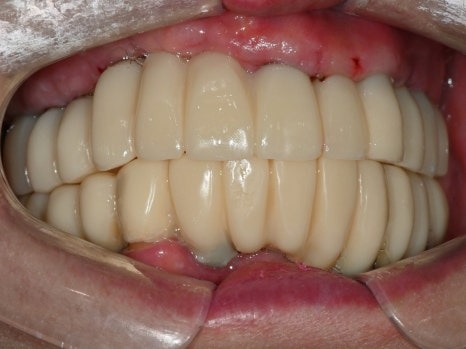

수술 후

디지털 방식으로 제작된 임시치아

8개의 전체임플란트를

하루에 바로 수술할 수 있었고,

병원 내의 디지털기공소에서

바로 임시치아를 제작하였습니다.

수술 전

수술 1일 후

하루만에 위턱 전체 치아가 생겨서

식사가 바로 가능하시게 되자

환자분은 너무 놀라워하시고 좋아하셨습니다.

디지털 임시치아는

컴퓨터(CAD) 상에서 디자인하고

3D 프린터, 밀링 머신(CAM)으로 가공하기 때문에

손으로 빚어서 만드는 임시치아보다

훨씬 단단하고 심미적이며,

임시치아라고 해도 3개월,

길게는 1년 이상까지도 사용하면서

임플란트 치아에 적응하는 시간도 가질 수 있습니다.